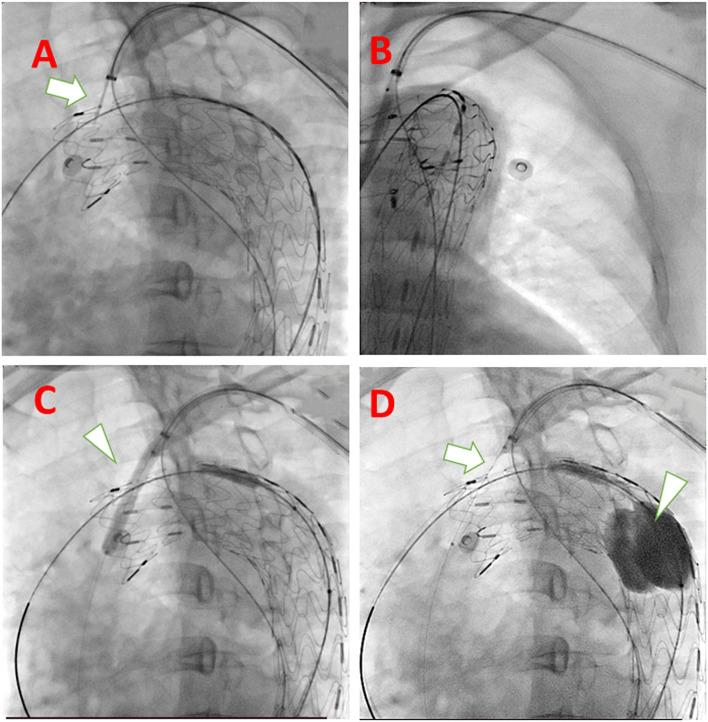

DESCRIPTION

The gutter-free stent-graft has a nickel-titanium self-expanding skeleton, double polytetrafluoroethylene coating, and an outer-skirt fabric structure (named C-skirt endograft). The outer skirt fabric prevents endoleak from the gutter around the stent graft fenestration. Further, the skirt structure right under the fenestration in the aortic stent graft can function as a fixation of the side-branch artery endograft. These designs have the following advantages, such as: 1) prevention of endoleak; and 2) fixation tightly between the branch and aorta endograft pieces.

EVALUATION

A patient who was diagnosed with an aortic arch aneurysm, combined with localized dissection, has successfully implanted the aortic stent graft and C-skirt endograft for the left subclavian artery. The 6-month follow-up result of the C-skirt in situ fenestration TEVAR is satisfactory without obvious endoleak.

评估

一名被诊断为主动脉弓瘤合并局限性夹层的患者成功植入了主动脉支架型人工血管及用于左锁骨下动脉的C裙边腔内移植物。C裙边原位开窗TEVAR的6个月随访结果令人满意,无明显内漏。